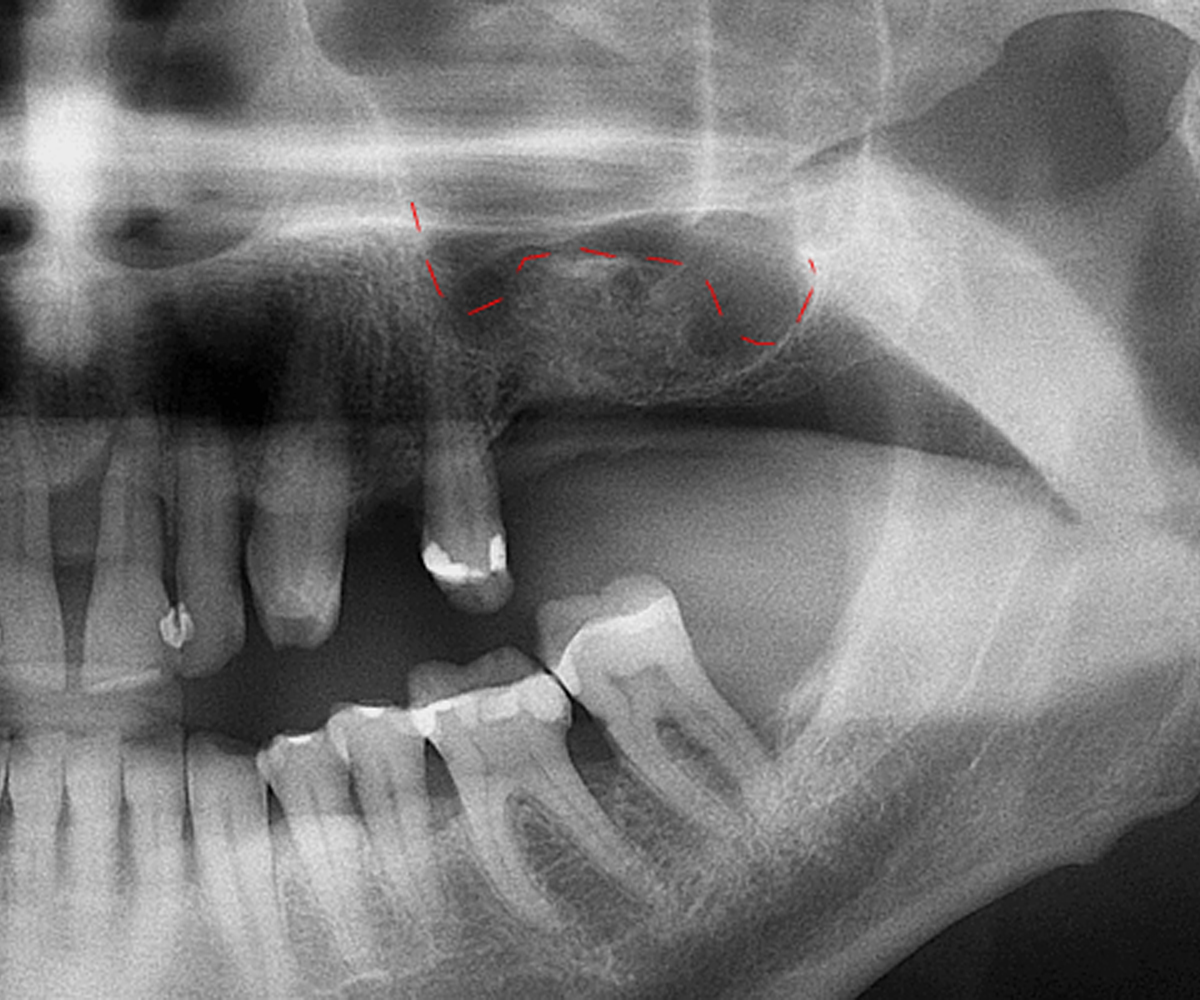

Il rialzo del seno mascellare è un intervento chirurgico che permette di aumentare la quantità di osso nella zona posteriore del mascellare superiore. Questo trattamento è spesso necessario per posizionare impianti dentali in pazienti che hanno perso volume osseo a causa di estrazioni, infezioni o riassorbimento naturale. Nel nostro studio la procedura viene eseguita con tecniche moderne e materiali sicuri, garantendo stabilità e risultati duraturi.

Il rialzo del seno mascellare è una soluzione fondamentale nei casi in cui l’osso non sia sufficiente per garantire la stabilità di un impianto. Intervenire con questa tecnica significa ridare solidità e funzionalità al sorriso, con un approccio sicuro e personalizzato.